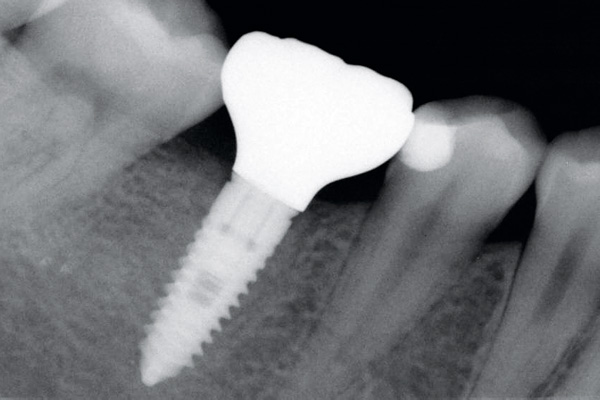

Delayed implant placement with GBR and soft tissue augmentation at the aesthetic area  -  2 years follow up – Dr. H. Maghaireh & Dr. V. Ivancheva

Initial situation - broken and missing upper right central incisor (UR1). This tooth was removed long time ago and there were signs of bone loss and resorption due to the bone remodelling. Patient was also undergoing orthodontic treatment due to the loss of mesio-distal space.